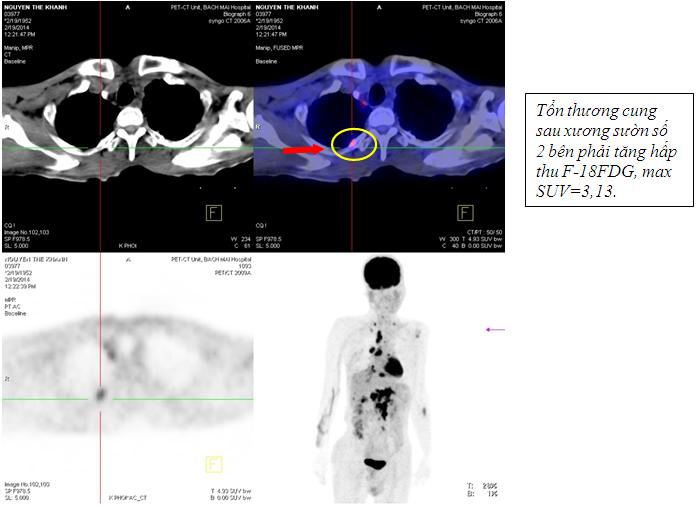

Kết quả chụp PET/CT: Khối vùng phế quản gốc phải KT 2,4x1,7cm; maxSUV=8,50; Hạch dưới carina KT 3,1x3,5cm ; maxSUV=8,50;Nhiều hạch ổ bụng dọc theo ĐMchủ bụng tạo thành khối lớn KT 8,5x5,1cm và 5,1x3,9cm, tăng hấp thu F-18 FDG, maxSUV=10,45; Hạch thượng đòn phải KT 1,1cm, tăng hấp thu F-18 FDG, max SUV=5,67; Hạch thượng đòn trái KT 0,8cm, max SUV=3,97; Tổn thương cung sau xương sườn số 2 bên phải tăng hấp thu F-18 FDG, max SUV=3,13; Nhu mô gan hạ phân thùy VI có nốt KT 1,2cm, tăng hấp thu F-18 FDG, max SUV=4,15.